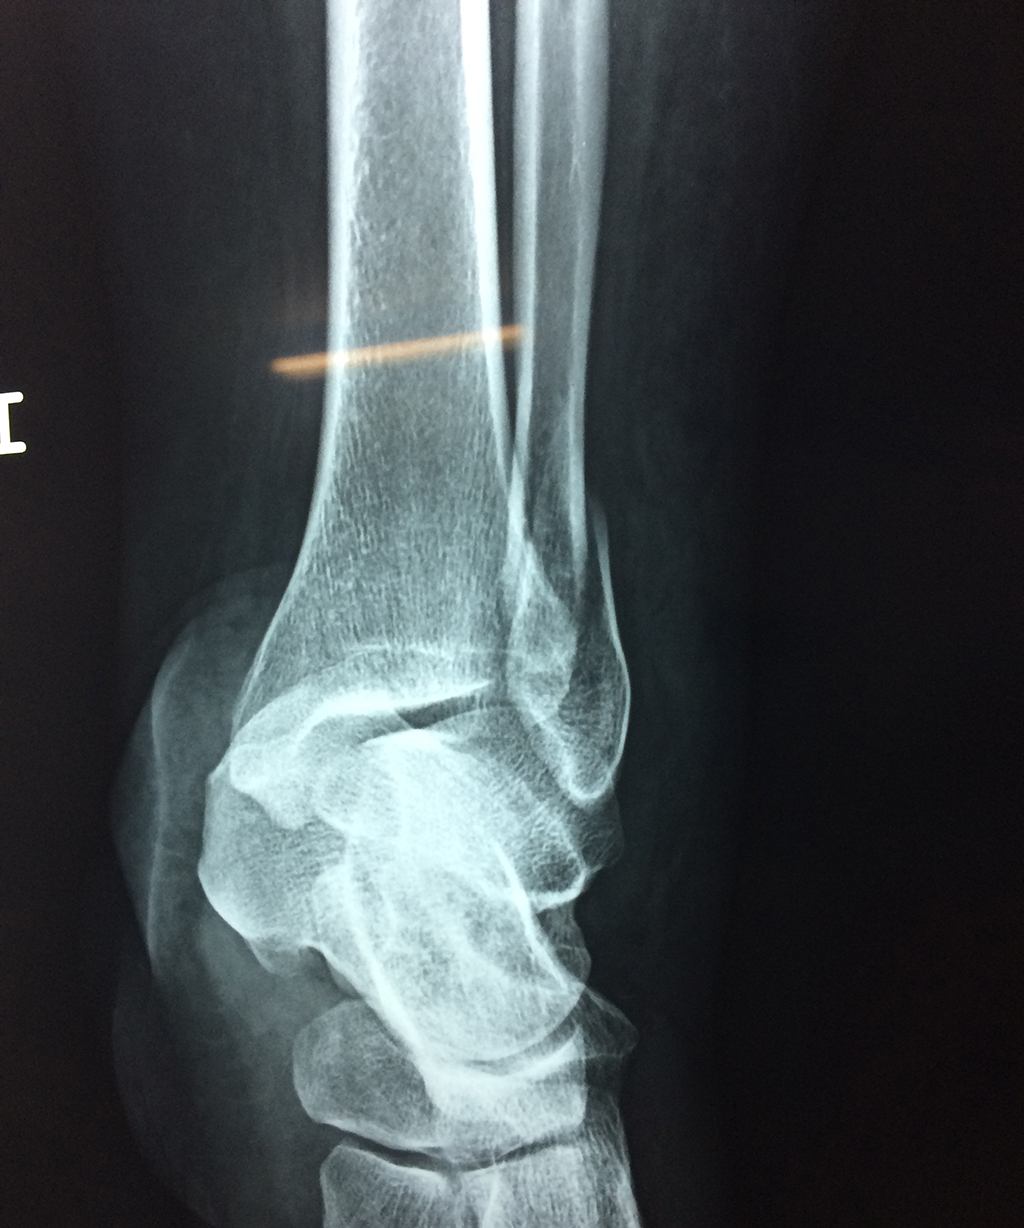

Algunas fracturas de tobillo pueden requerir cirugía si:

- Los extremos de los huesos están desalineados entre sí (desplazados).

- La fractura se extiende hasta la articulación del tobillo (fractura intra-articular).

- Los tendones o ligamentos (tejidos que sujetan los músculos y los huesos entre sí) están rotos.

- El médico cree que sus huesos probablemente no sanen apropiadamente sin cirugía.

- El médico considera que la cirugía puede permitirle una recuperación más rápida y confiable.